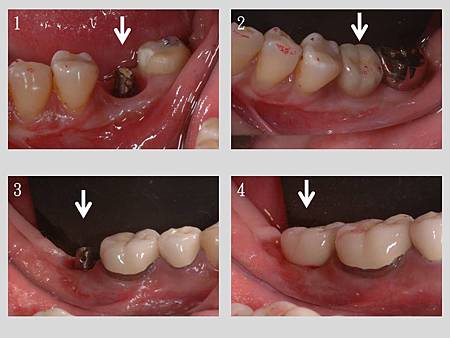

患者因先前製作的牙橋又蛀進去而牙痛, 拆除牙橋後評估現況, 若重新以一樣設計再做一個橋的話使用年限會非常的短, 所以與患者溝通後採用人工植牙方式解決問題(增加地基數量減輕自然牙負擔, 力量跟清潔都會改善許多), 常常可以看到像這樣前傾的臼齒, 這是因為前方的牙齒拔掉後沒有第一時間製作假牙, 後方的牙齒會往前傾倒, 所以使用骨釘將前傾的牙齒拉回原位, 缺牙區再使用人工植牙恢復咬合

如圖, 銀色的牙齒是下顎第二大臼齒(使用骨釘往後拉), 前方空間恢復後植入人工植牙

治療前後比較, 注意觀察第二大臼齒與前方第二小臼齒的角度前後差異